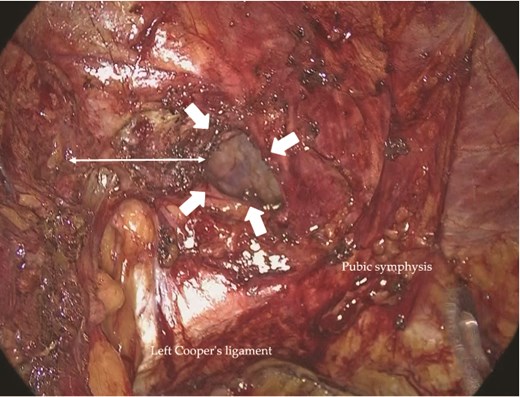

Under general anesthesia, a 12-mm camera port was inserted through the umbilicus, and two 5-mm ports were placed in the lower quadrants. Laparoscopic exploration revealed two mesh plugs on the left with fibrotic scarring and adhesions, which obscured the exact hernia orifice (Fig. 2). An incidental right direct hernia (M3) was also identified intraoperatively. Because severe adhesions were anticipated on the left, the operation was initiated on the right. A high peritoneal incision was initiated medial to the right anterior superior iliac spine (Fig. 3). The pseudosac was dissected while preserving the retropubic fascia, and the preperitoneal dissection was extended across the midline into the left side (Fig. 4). Approaching from the contralateral side allowed progressive entry into the adhesion-laden region through an unscarred plane, improving visualization and minimizing peritoneal injury.

Laparoscopic view of the left inguinal region showing two previously placed mesh plugs (arrows). No definite recurrent hernia orifice was identified. Dense adhesions were present around the plugs.